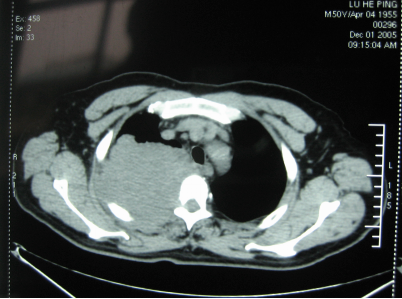

手术前CT显示

“肿瘤大小约10×10cm,虽然已经错过最佳治疗时间,但所幸来得及时,不然就真的无力回天。”当天徐克成荣誉总院长、牛立志院长针对鲁叔的病情组织专家会诊,决定1月7日采用冷冻消融治疗术+碘粒子疗法为鲁叔治疗。